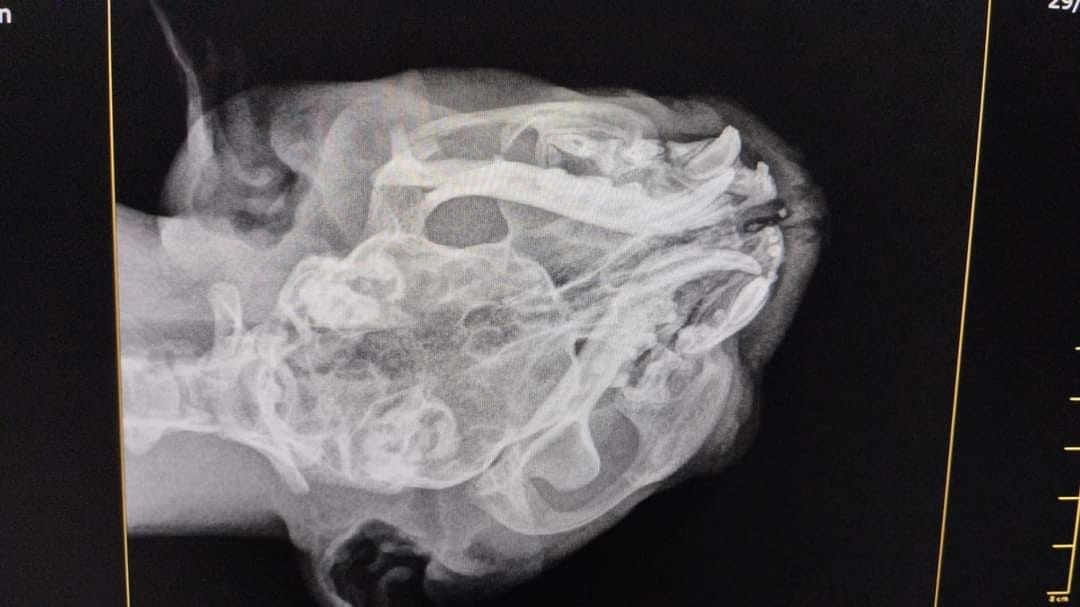

En este sentido, el gatito cuenta con fractura en ambos maxilares, tiene el paladar partido por dentro en 2 fracciones, lo que le genera problemas con la respiración, pues la lesión llegó hasta los conductos nasales por lo que será sometido a cirugía.